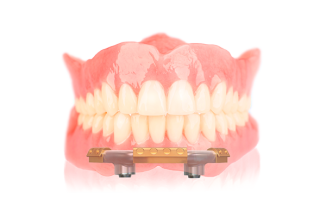

Met de AvaDent immediaat prothese kan de bestaande dentitie eenvoudig worden overgenomen. Dankzij de digitale back-up kunnen kleur, stand en vorm worden overgenomen bij het vervaardigen van de uiteindelijke prothese. De immediaat prothese is volledig monolitisch, tot wel 8 keer sterker en zorgt voor minder last van drukplekken.

AvaDent immediaat prothese

Immediaat prothese